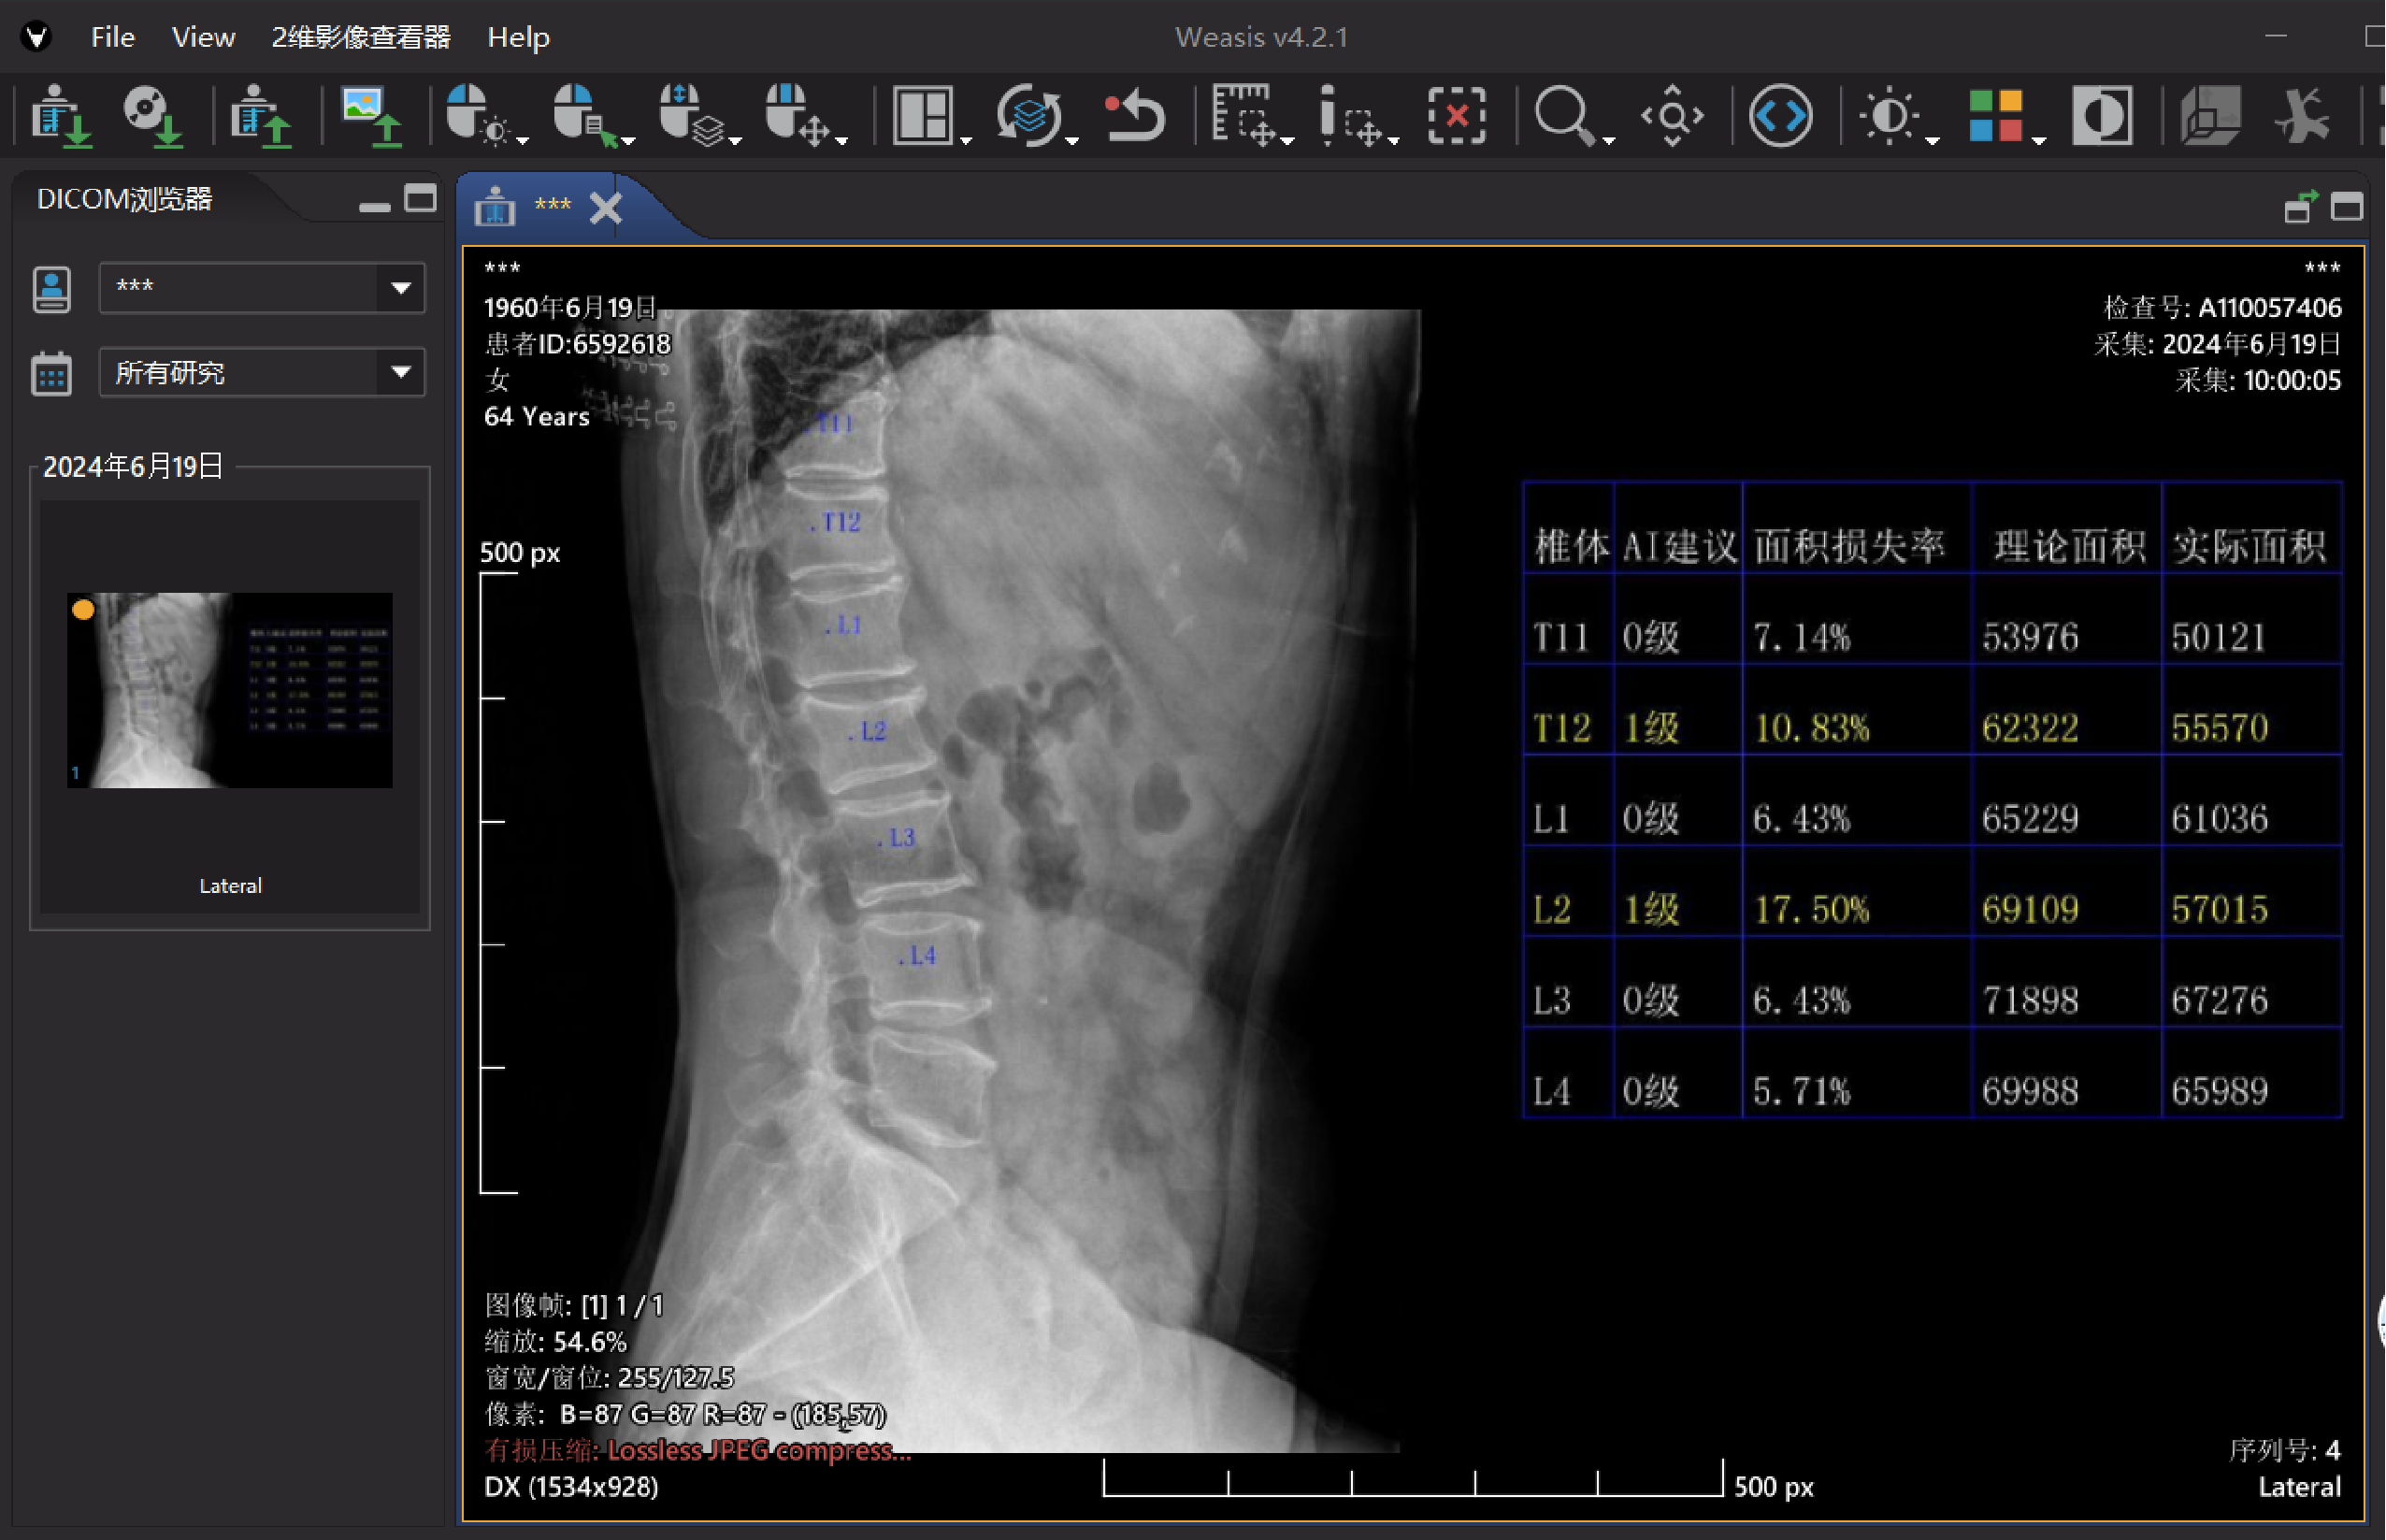

骨质疏松性椎体骨折辅助诊断系统(基于CT)

基于CT侧位定位像,运用深度学习算法对椎体骨折进行智能识别与精准分度,能快速辅助医生完成影像评估,提升骨质疏松性椎体骨折的诊断效率与一致性。